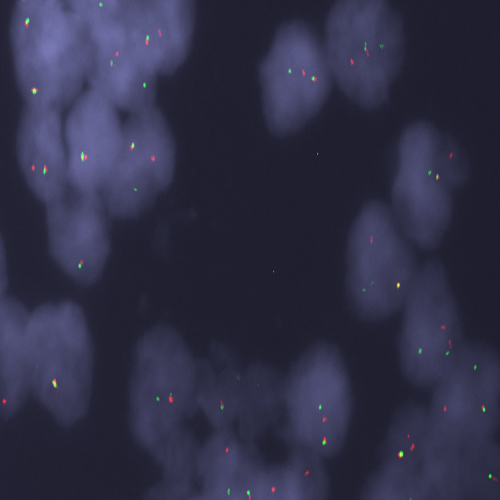

Human medullary thyroid carcinoma: immunohistochemical staining for Calcitonin. Calcitonin: clone CL1948

Calcitonin (CT) is a 32 amino acid peptide synthesized by the parafollicular C cells of the thyroid. It acts through its receptors to inhibit osteoclast mediated bone resorption, decrease calcium resorption by the kidney and decrease calcium absorption by the intestines. The action of calcitonin is therefore to cause a reduction in serum calcium, an effect opposite to that of parathyroid hormone. The calcitonin gene transcript also encodes the calcitonin gene-related peptide (CGRP), which is thought to be a potent vasodilator. The tissue specificity of the transcript produced depends on alternative splicing of the CT/CGRP gene transcript. In the parafollicular cells of the thyroid 95% of the CT/CGRP is processed and translated to produce CT, however, in neuronal cells 99% of the CT/CGRP RNA is translated into CGRP. The C cells of the thyroid give rise to an endocrine tumor, medullary thyroid carcinoma (MTC), which occurs in a sporadic (75% of cases) and hereditary form (25% of cases). Familial MTC is associated with C cell hyperplasia (CCH), whereas sporadic MTC is thought not to be. However, in the general population CCH is present in 20-30% of thyroid glands, either with normal histology, thyroiditis or follicular tumors.